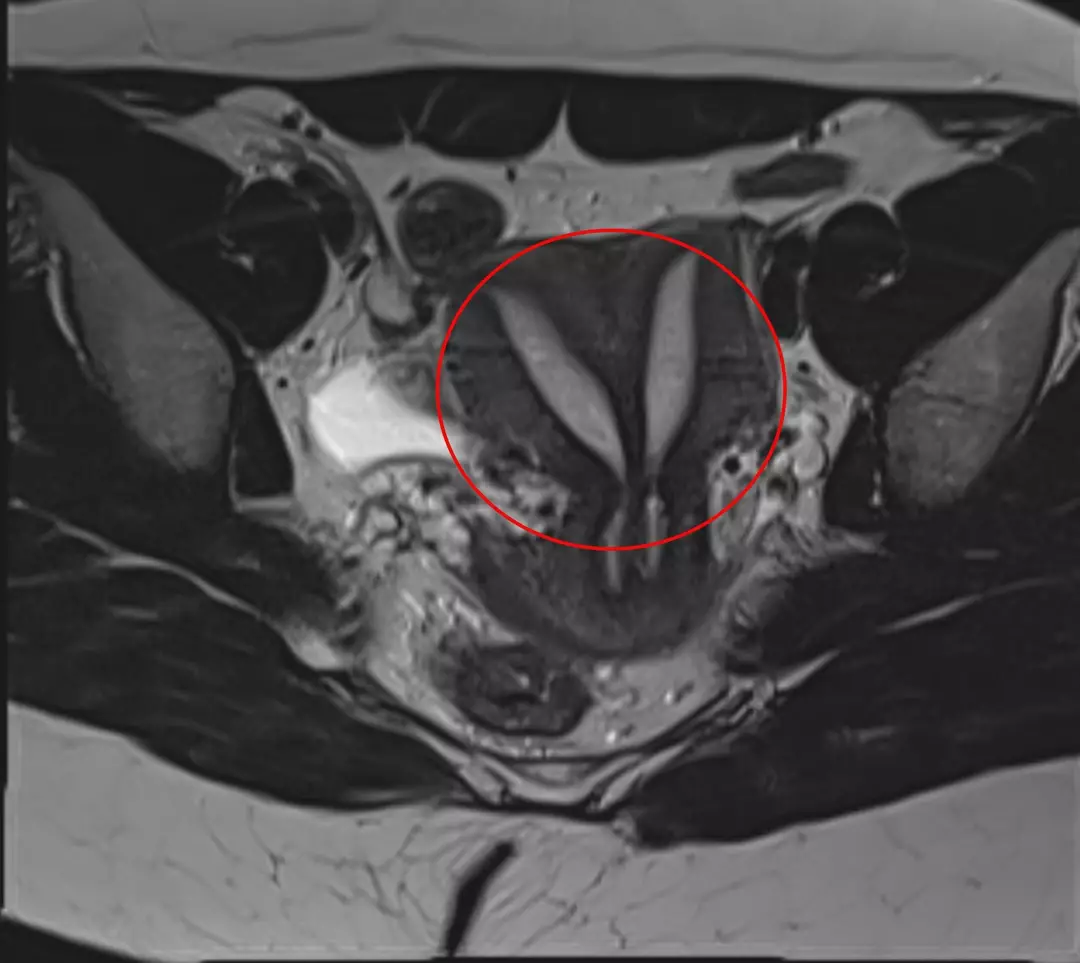

At 27, she has been living with complete uterus didelphys, a rare congenital condition where an individual is born with two uteruses, as described by Cleveland Clinic.

This condition, also known as ‘double uteruses,’ affects only about 0.3 percent of the American population.